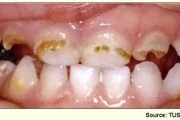

Vali sind huvitav pilt ja me näitame sellega seotud haigust ja sümptomeid